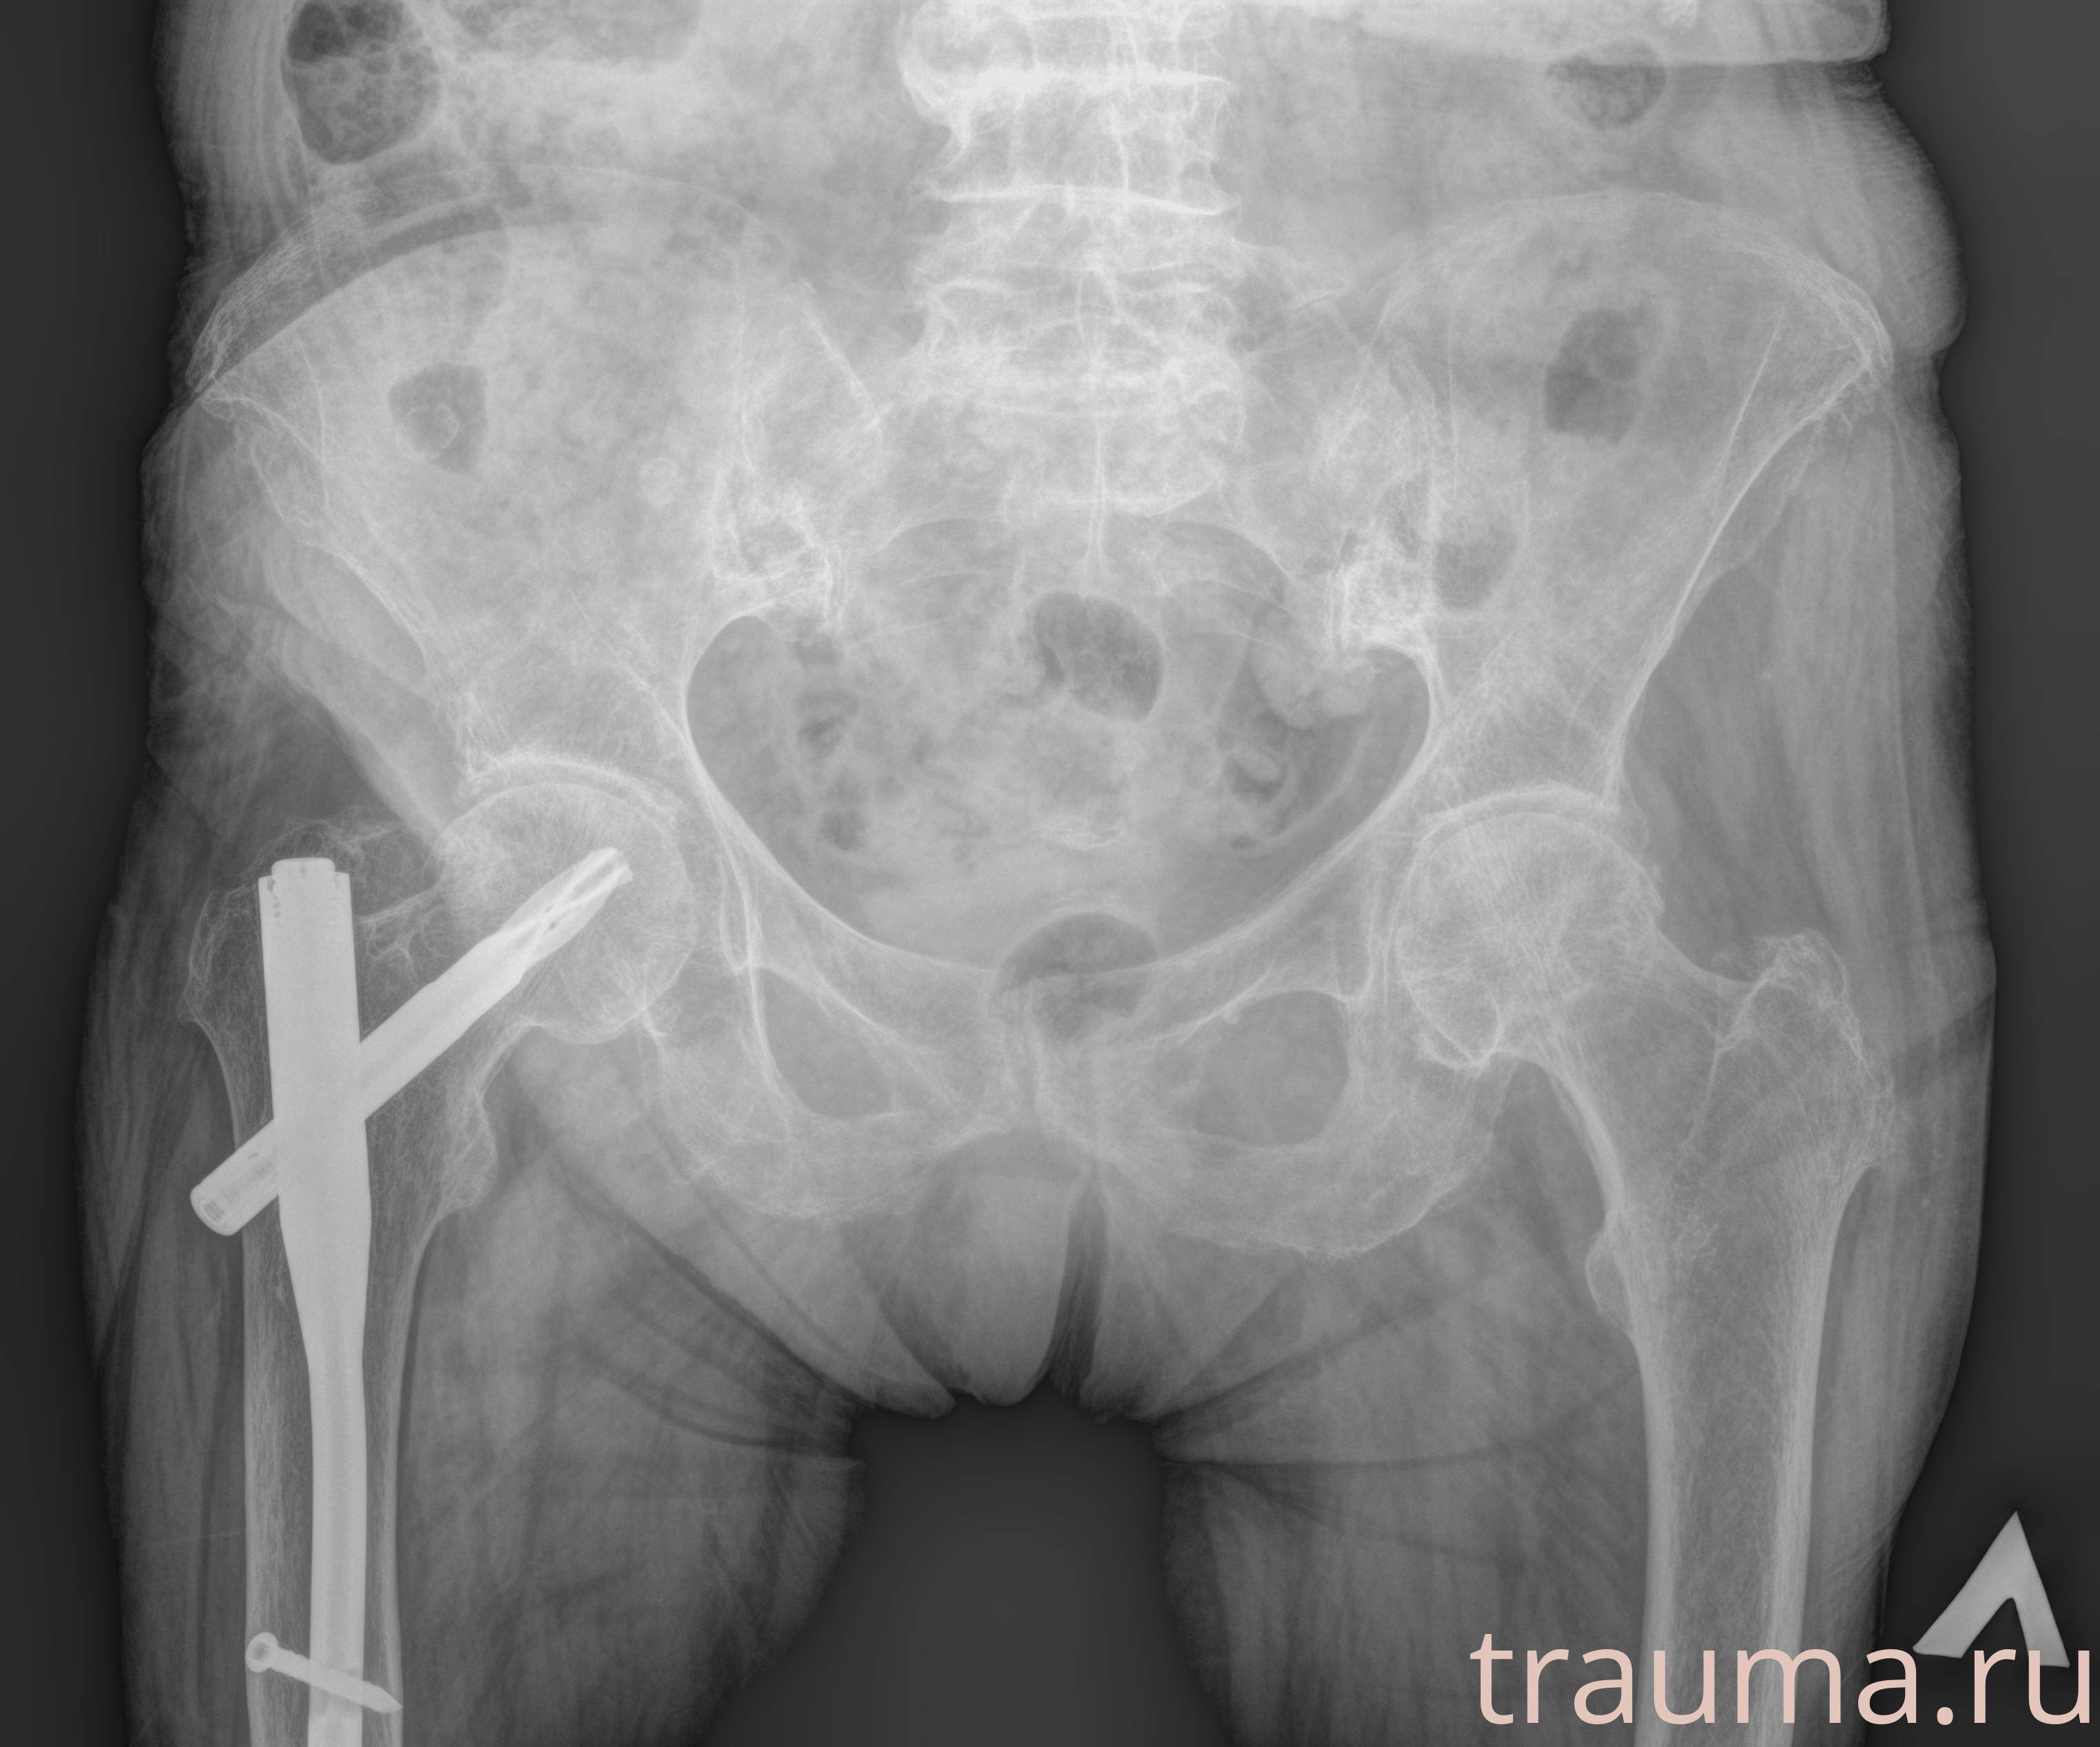

Рентгенограммы

Рентген на дому: по вашему адресу приезжает врач-рентгенолог, травматолог-ортопед с мобильным рентгеновским аппаратом, проводит диагностику травмы или заболевания, делает необходимые рентгенограммы, дает рекомендации по дальнейшему лечению. Получить качественные снимки в домашних условиях возможно благодаря уникальной методике, разработанной МосРентген Центром для института  Склифосовского